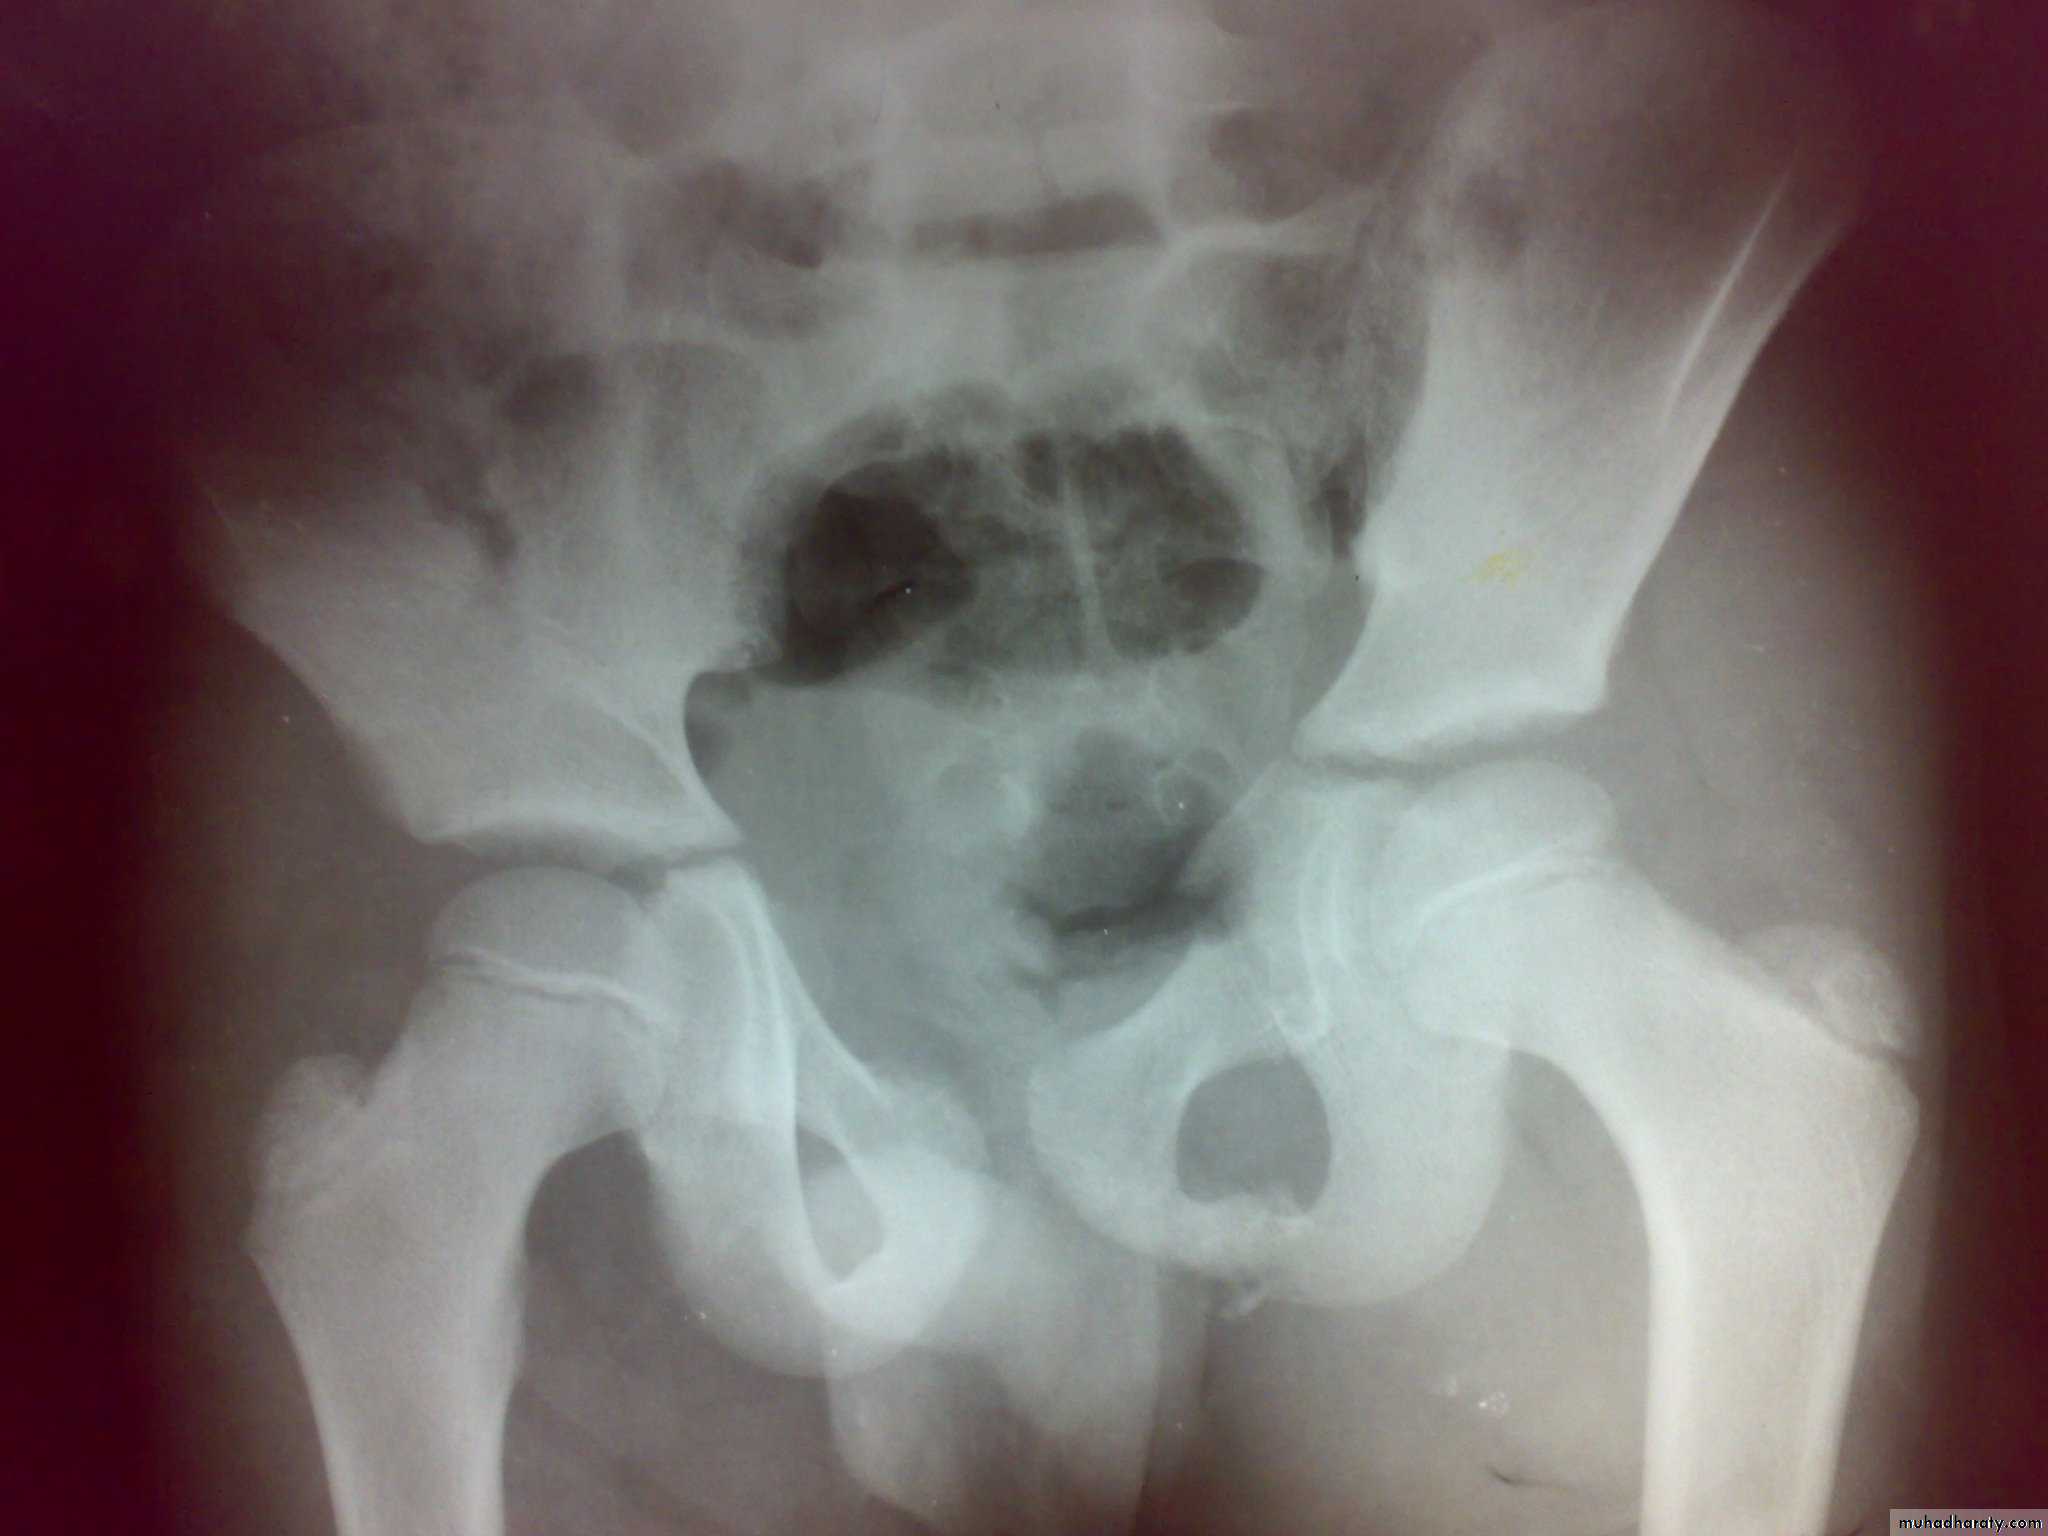

Fracture acetabulum

Fracture pubic rami